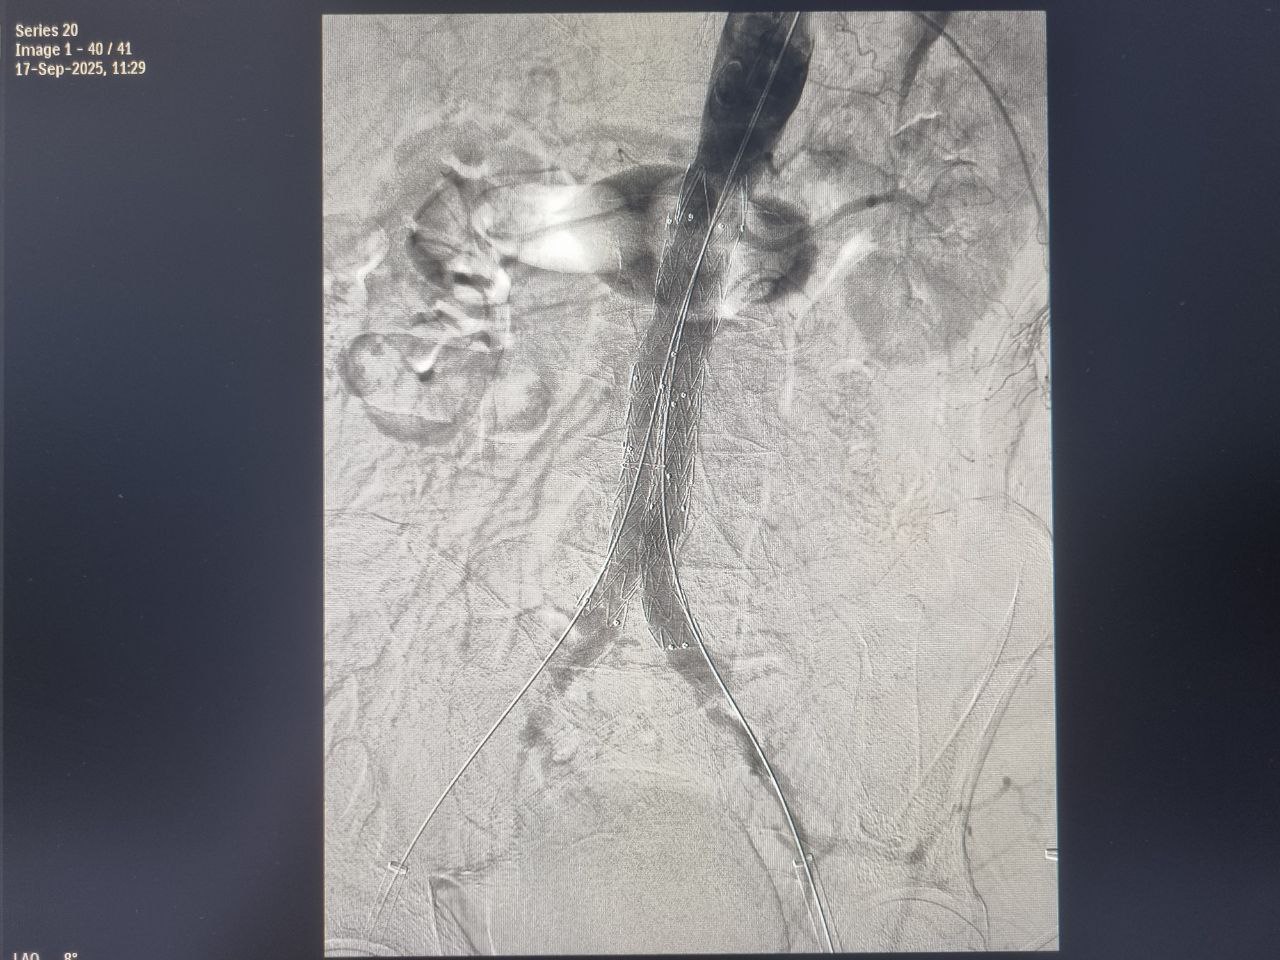

В рамках реализации федерального проекта «Борьба с сердечно-сосудистыми заболеваниями» национального проекта «Продолжительная и активная жизнь»  врачи-регионального сосудистого центра Клинической больницы №6 имени Г.А. Захарьина провели высокотехнологичное оперативное медицинское вмешательство, выполнив протезирование участка брюшной аорты.

У мужчины 68 лет в ходе углублённой диспансеризации было выявлено подозрение на аневризму брюшной аорты.

После тщательного обследования в ходе ангиографического исследования у пациента были обнаружены признаки нестабильности в просвете аневризмы, а также критическое поражение устья левой почечной артерии, вовлеченное в аневризму брюшной аорты.

Коллегиально специалистами больницы было принято решение провести эндопротезирование брюшного отдела аорты с переходом на подвздошные артерии и стентирование левой почечной артерии при помощи эндоваскулярного пособия. Чтобы снизить риск угроза разрыва и внезапной смерти.

На протяжении трех часов хирургическая бригада в составе врача-сосудистого хирурга Олега Костенко, врача-рентгенохирурга Игоря Илясова и врача - анестезиолога-реаниматолога Артура Полича проводила эндопротезирование.

«Одной из альтернатив открытых хирургических операций для лечения аневризмы аорты на данный момент является эндоваскулярное протезирование с установкой в зоне аневризмы стент-графта (металлической сетки, покрытой изнутри полимерной тканью). Такая конструкция создает каркас внутри сосуда и предотвращает риск разрыва аневризмы», - говорит Игорь Борисович.

По словам специалиста, операция проводится через небольшие разрезы на бедре под спинальной анестезией. «По сравнению с открытыми хирургическими вмешательствами эндоваскулярное протезирование имеет более низкий риск осложнений, связанных с временной остановкой кровообращения в жизненно важных органах и нижних конечностях, меньшую кровопотерю и быструю реабилитацию», - уточняет Игорь Илясов.

«После операции у пациента произошла эпителизация металлического каркаса стентов и усиление стенки сосуда при сохранении диаметра артерии», - поделился врач.